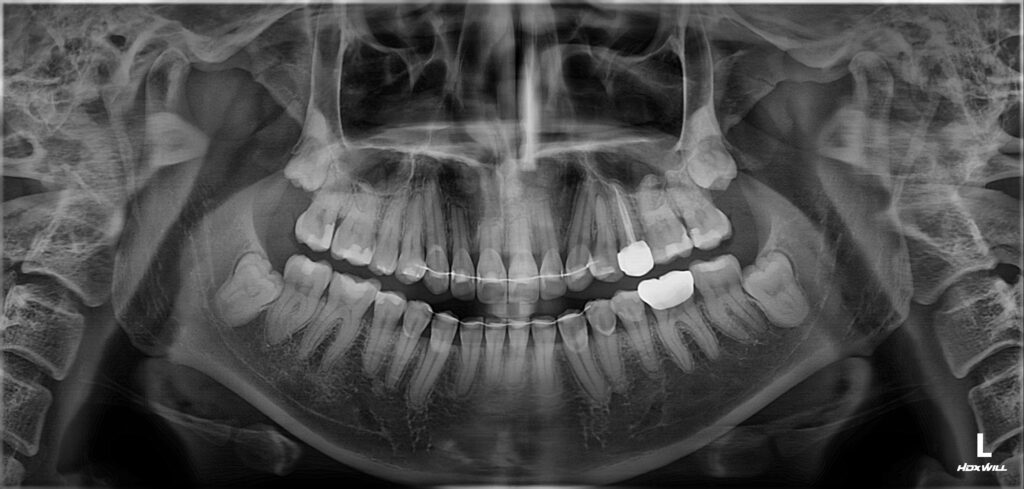

치아 색상 불균형과 심미적 불만족을

주소로 구강 내 검진 결과,

상악 전치부에는 눈에 띄는 착색과 함께

치경부 우식이 다수 관찰되었으며,

일부 치아에서는 구조적인 손상까지

동반된 상태였습니다.

전체적으로 인레이 6개, 근관치료 1개,

크라운 2개, 레진 6개 등 총 20개 치아에 대한

치료가 이루어졌으며,